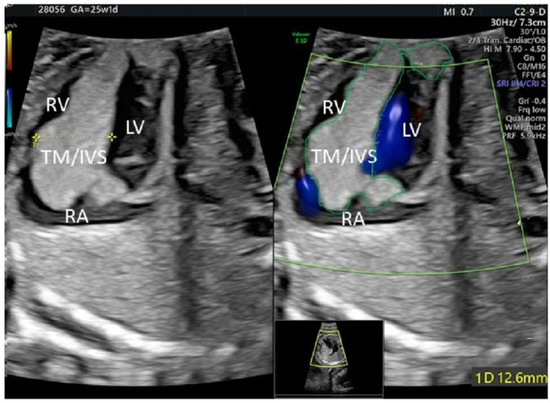

2. Case Description